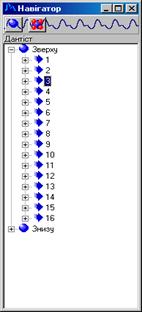

Рисунок 8.2 – Карта розміщення хребців

Після реєстрації з^явиться вікно "Навігатор" в якому активні елементи розміщенні по групам. Так навігатор для вертебродіагностики представлений на рисунку 8.2. Можливим є створення структур для навігатора довільної форми (різне число секцій й підсекцій) [17, 18].

Переміщення по навігатору відбувається з допомогою клавіатури або маніпулятора "миша". Після вибору певного елемента 3-го рівня навігатора ("До сеансу" або "Після сеансу") можна приступати до зняття ФПГ даних.